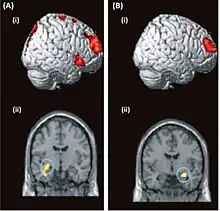

| Brain-imaging data from two patients with dissociative amnesia | |

Brain activity can be assessed functionally for psychogenic amnesia using imaging techniques such as fMRI, PET and EEG, in accordance with clinical data.[6] Some research has suggested that organic and psychogenic amnesia to some extent share the involvement of the same structures of the temporo-frontal region in the brain.[7] It has been suggested that deficits in episodic memory may be attributable to dysfunction in the limbic system,[21] while self-identity deficits have been suggested as attributable to functional changes related to the posterior parietal cortex.[3] To reiterate however, care must be taken when attempting to define causation as only ad hoc reasoning about the aetiology of psychogenic amnesia is possible, which means cause and consequence can be infeasible to untangle.[15]